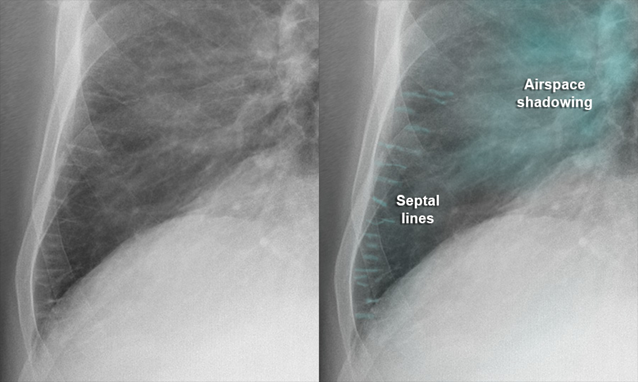

Hình ảnh đường Kerley B: là các đường mờ ngắn, nằm ngang ở vùng đáy phổi trên X-quang ngực, thường gặp trong phù kẽ phổi – đặc biệt là phù phổi do tim. Nguồn: Tetaj, N., et al. (2026). Respiratory support in cardiogenic pulmonary edema. Journal of Cardiovascular Development and Disease, 13(1), 54